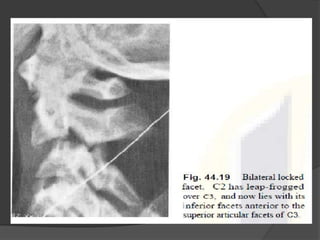

Bilateral facet Lock

Unilateral facet dislocation